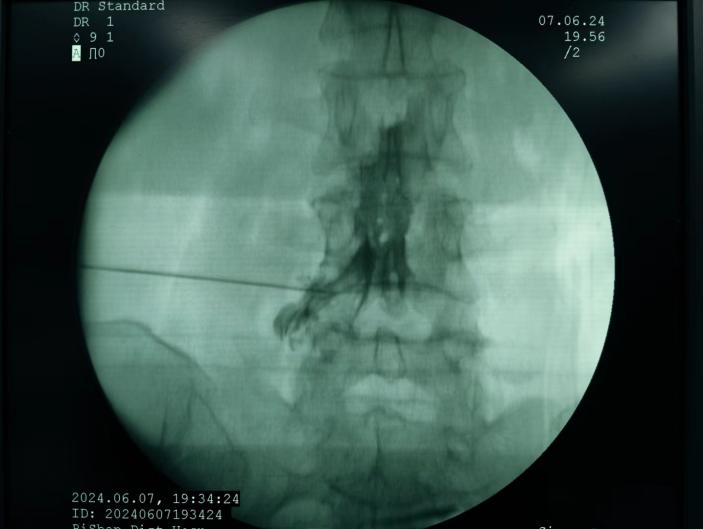

膠原酶椎間盤化學(xué)溶解術(shù),是在影像引導(dǎo)下(C型臂X線機(jī)或CT),將膠原酶準(zhǔn)確地注射到突出的椎間盤內(nèi)及其周圍,使突出的椎間盤溶解并吸收,解除其對神經(jīng)根的壓迫,進(jìn)而緩解癥狀。

椎間盤射頻消融術(shù)、膠原酶椎間盤化學(xué)消融術(shù)